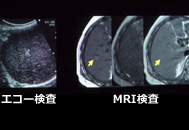

- 画像診断:腹部超音波検査(エコー検査)、CT/MRI、血管造影(カテーテル検査)

肝臓がんの画像診断

画像を組み合わせることで早期診断が可能